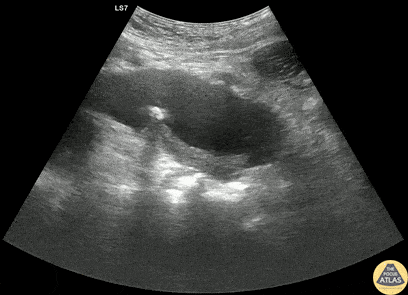

Aorta - Thrombosed Type B Aortic Dissection

60s M PMH HTN, CKD stage 3 presented with bilateral flank pain x2 days. CT of the abdomen/pelvis with IV contrast showed a 3.8 cm x 4.6 cm infrarenal AAA with a 3.1 cm L internal iliac aneurysm. POCUS of the aorta was obtained re-demonstrating the AAA. Dedicated CTA showed that there actually demonstrating aneurysmal dilation of the descending thoracic aorta with a thrombosed type B dissection. The patient was managed with aggressive blood pressure and heart rate control with esmolol and was admitted to the ICU for medical management. Dr. Henrik Galust, PGY4, Denver Health Residency in Emergency Medicine Dr. Nimish Bhatt, Fellow, Denver Health Ultrasound Fellowship